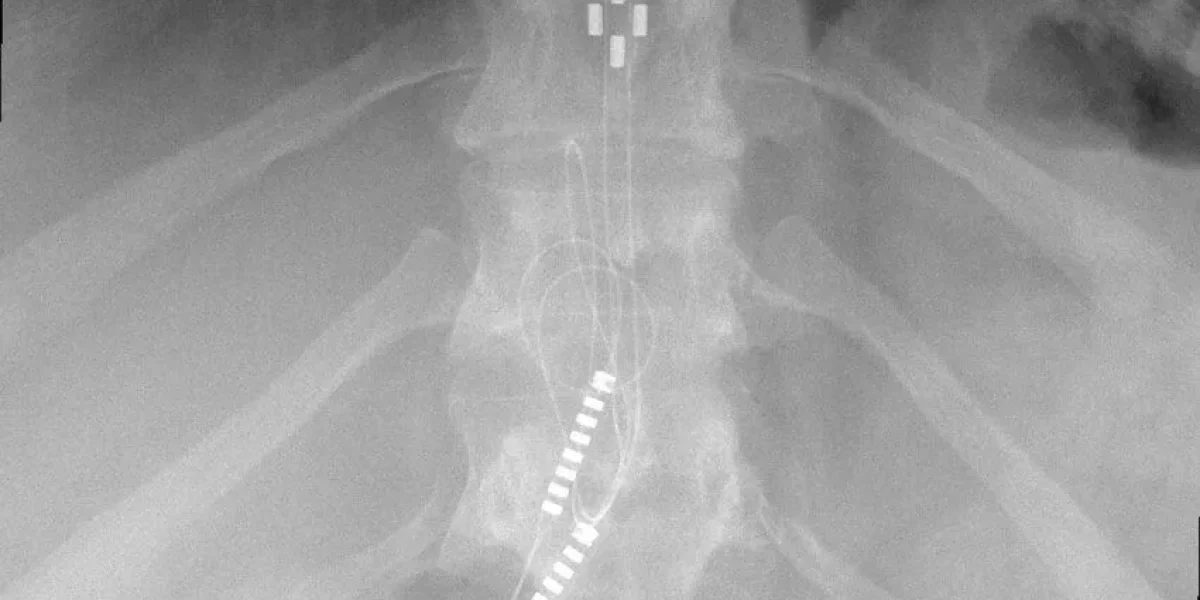

HF10 therapy involves implanting a device near the spine, sending high-frequency electrical signals to silence nerves that cause chronic pain. Electrical leads are placed at the particular nerves causing the patient’s persistent pain, and a separate battery pack is implanted to give electrical current. The HF10 device may be controlled and turned off using a remote control.

In this surgical procedure, insulated wires are inserted within reach of the spinal cord. These wires are connected to a small, battery-powered pulse generator implanted just under the skin. HF10 spinal cord stimulation sends mild electrical pulses to the spinal cord, calming the nerves and allowing them to return to a more normal, relaxed state.